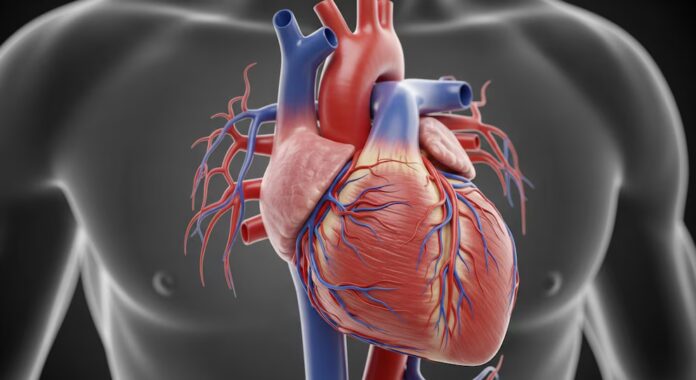

La mayoría de las personas no se preocupan por las enfermedades cardíacas durante sus 20, 30 o incluso 40 años. Quizás piensen que es algo que pueden ignorar sin problema hasta la mediana edad y más allá.

Sin embargo, nuevas investigaciones sugieren que, para muchos hombres, el riesgo de padecer enfermedades cardíacas puede empezar a aumentar antes de lo que ellos —o incluso sus médicos— se dan cuenta.

Un estudio de décadas de duración, dirigido por investigadores de Northwestern Medicine y publicado este año en el Journal of the American Heart Association, reveló que los hombres comienzan a desarrollar enfermedades cardiovasculares (ECV) años antes que las mujeres, y que las diferencias en el riesgo cardíaco comienzan ya a mediados de los 30 años.

El factor principal que incrementa el riesgo de sufrir un infarto a una edad más temprana en los hombres es una mayor incidencia de enfermedad coronaria (EC), que se produce cuando se acumula placa en las paredes de las arterias del corazón.